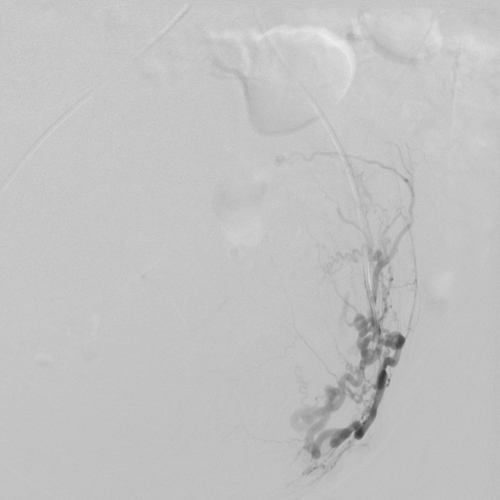

2014 թ. սեպտեմբերի15-ին «Էրեբունի» բժշկական կենտրոնում հերթական բացառիկ վիրահատությունն է անցկացվել՝ արգանդային զարկերակների էմբոլիզացիա՝ արգանդի միոմայի պատճառով: Այս էնդովասկուլյար միջամտությունը միոմայի բուժման արմատական մեթոդներից է:

2014 թ. սեպտեմբերի10-ին 52-ամյա Գ.Օ. «Էրեբունի» բժշկական կենտրոն դիմեց արգանդի միոմա, մետրոռագիա, լյարդի աջ մասի հսկայական հեմանգիոմա ախտորոշմամբ: Հիվանդի վիճակը ծանր էր, անընդմեջ արյունահոսության պատճառով նրա մոտ զարգացել էր նաև սակավարյունություն: Հիվանդին կրկնակի արյան փոխներարկում էր իրականացվել, ինչից հետո միայն հնարավոր էր դարձել վիրահատության իրականացումը:

Հիվանդին հակացուցված էր բաց վիրահատության ճանապարհով արգանդի հեռացում իրականացնել, քանի որ վիրահատության ընթացքում հեմանգիոմայի վնասման ռիսկը մեծ էր, ինչն իր հերթին կարող էր զանգվածային արյունահոսության պատճառ լիներ:

Վիրահատության տևողությունը 30-40 րոպե է: Վիրահատության էությունը երկու արգանդային զարկերակների էմբոլիզացիա կատարելն է՝ չխախտելով արյան շրջանառությունն արգանդում: Այն նվազագույն միջամտություն պահանջող և քիչ վնասվածքներ հարուցող վիրահատություն է, որն իրականացվում է տեղային անզգայացմամբ: Վիրահատությունը հնարավորություն է ընձեռում խուսափել հիստեէկտոմիայից (արգանդի հեռացումից), առավել ևս, երբ կինը դեռ վերարտադրողական տարիքում է գտնվում: Այսպիսի վիրահատություններ կարելի է անցկացնել ինչպես եզակի միոմայի, այնպես էլ ցանկացած տեղայնացման արգանդի միոմատոզի ժամանակ:

Վիրահատությունն անց է կացվել փորձառու ինվազիվ սրտաբան Արսեն Ծատուրյանի կողմից, ով բազմիցս իրականացրել է վերոնշյալից ոչ պակաս բարդ վիրահատություններ և որոնց դրական արդյունքները խոսում են նրա պրոֆեսիոնալիզմի մասին:

Հետվիրահատական շրջանն անցել է հարթ՝ առանց բարդությունների: Հիվանդը երկու օր գտնվել է շուրջօրյա հսկողության տակ, այնուհետև դուրս է գրվել՝ շարունակելով մնալ բժիշկների ուշադրության կենտրոնում:

Անհրաժեշտ է նշել, որ այսպիսի վիրահատություն Հայաստանում առաջին անգամ է իրականացվել: